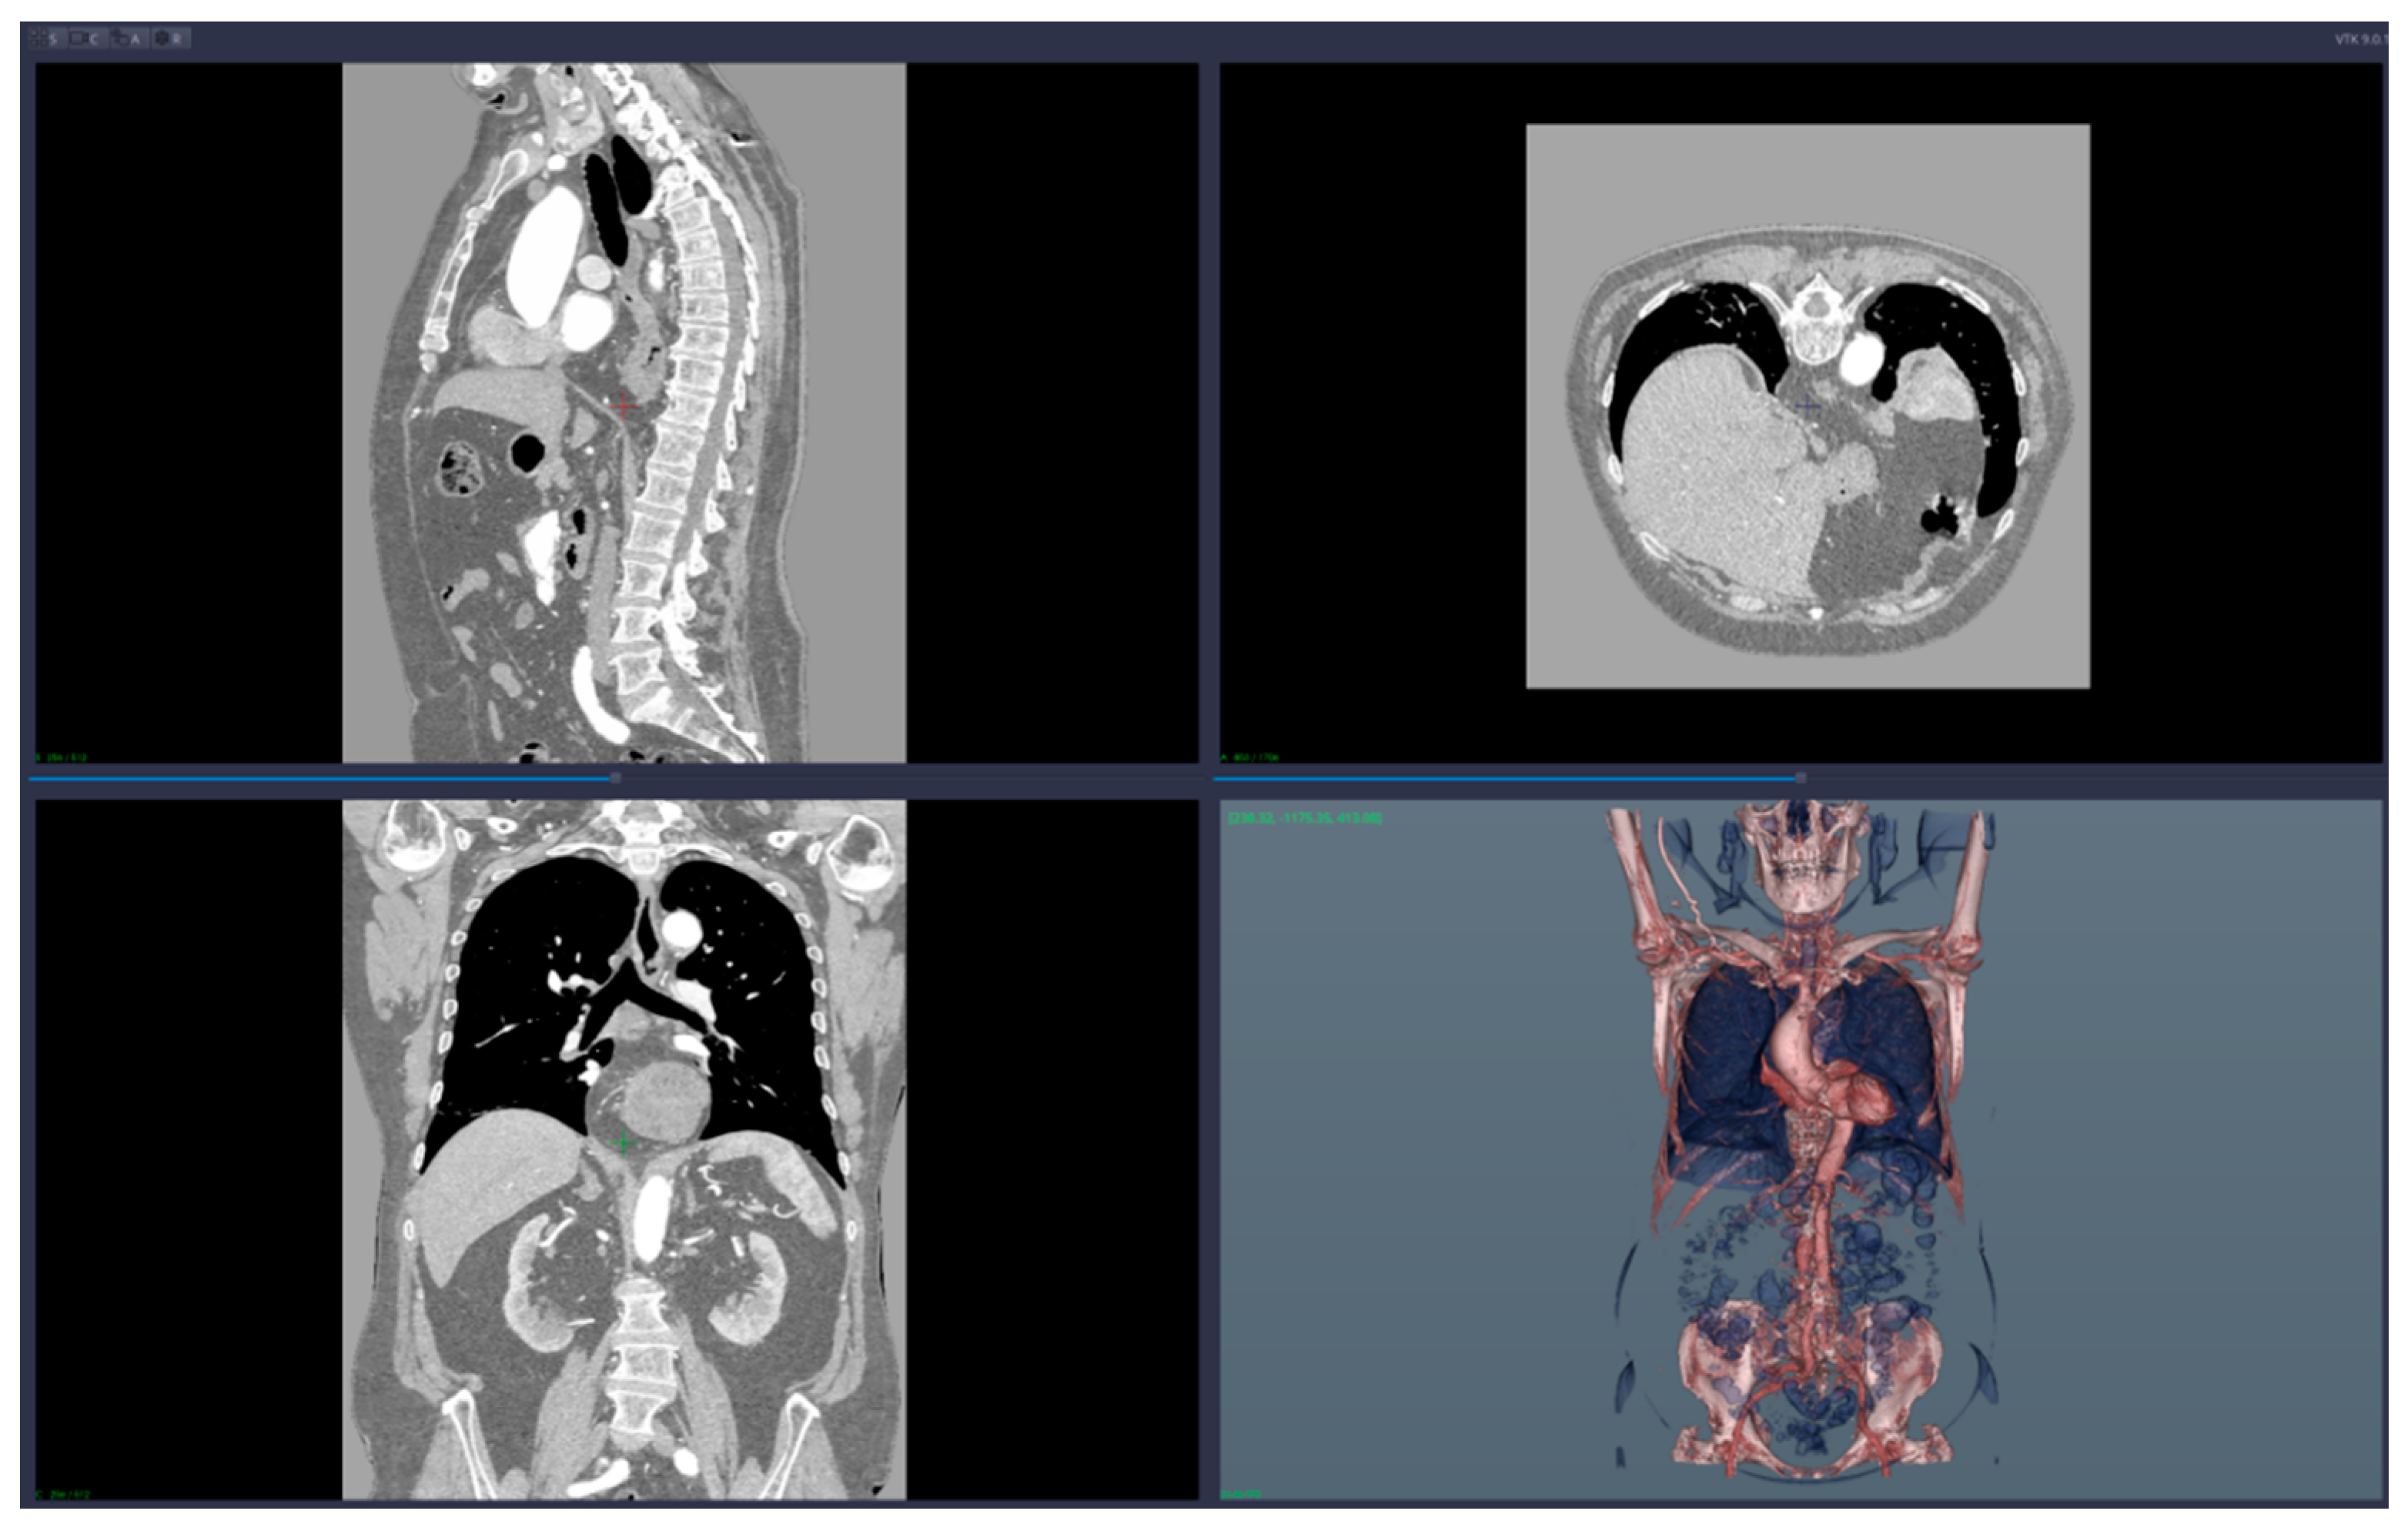

• 3D reconstruction and visualization of arteries (see Figure 1 and Figure 2)

We applied the suggested pre-operatory planning procedure on CT data from a male patient aged 74. The scans were performed using a Siemens Somatom go. Top 128 slice machine [18], with contrast substance (ULTRAVIST 370 I.V.). The series used for planning took 647 slices at a distance of 0.99 mm each. The reconstructed 3D image had 655 × 512 × 647 voxels.

Figure 1. Images of the 3D CT reconstruction and 2D sections.